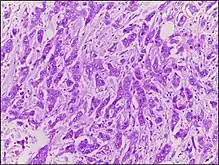

| Micrograph of breast tissue with ductal carcinoma. H&E stain. |

Ductal carcinoma is a type of tumor that primarily presents in the ducts of a gland.[1]